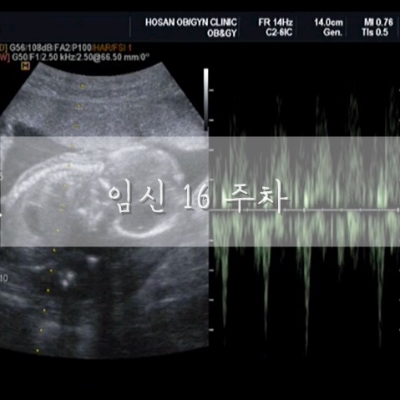

임신 16주 :: 성별 확인, 2차 기형아 검사

임신 16주차 증상태동 시작 성별 확인 살 찌기 시작 완전한 안정기 몸무게 46.5kg 혈압 98/57 임신전 44kg...